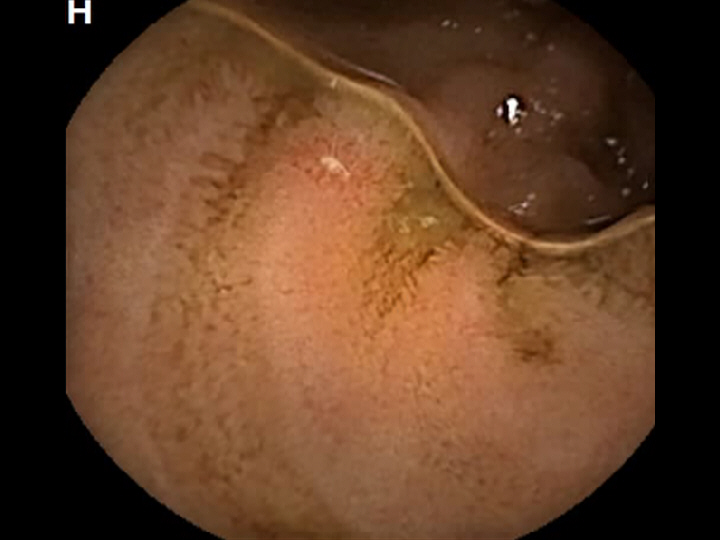

CAPSULE ENDOSCOPY: Crohns Disease: Aphthous Ulcerations in the Small Bowel

Crohns Disease: Aphthous Ulcerations in the Small Bowel. Just click on a picture!

Crohns Disease: Aphthous Ulcerations in the Small Bowel